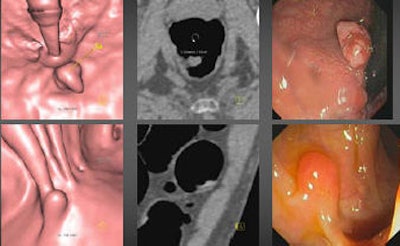

| A 70-year-old asymptomatic woman presented with nine polyps at both OC (left) and VC (middle and right), including four larger than 2 cm. FOBT and FIT were positive; however, flexible sigmoidoscopy found only five of nine lesions. All images courtesy of Dr. Anno Graser. |

"We detected 147 adenomas ≤ 5 mm and 42 adenomas 6-9 mm in size," Graser noted in an e-mail to AuntMinnie.com. "Thirteen of these small and medium adenomas were of advanced histology. The other 33 (72%) advanced adenomas were ≥ 10 mm."

In 27 subjects, there were 36 adenomas 9 mm or larger (total of 40 polyps > 9 mm). There were 79 adenomas larger than 5 mm (total 100 polyps > 5 mm in 61 subjects), for a total of 80% of lesions smaller than 6 mm. Only 9% were 6-9 mm, and 7.8% were larger than 9 mm. Only about half of the adenomas were within the range of the flexible sigmoidoscope, Mang said.